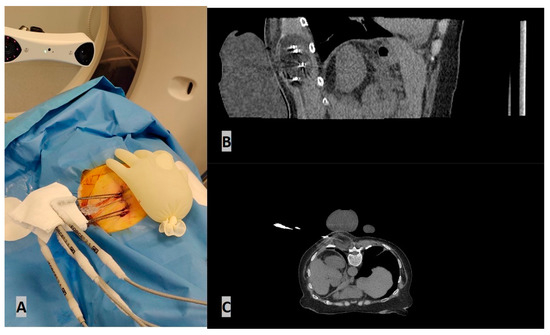

- Grigoriadis, S.; Filippiadis, D.; Stamatopoulou, V.; Alexopoulou, E.; Kelekis, N.; Kelekis, A. Navigation Guidance for Percutaneous Splanchnic Nerve Radiofrequency Neurolysis: Preliminary Results. Medicina 2022, 58, 1359. [Google Scholar] [CrossRef]

- Bale, R.; Widmann, G. Navigated CT-guided interventions. Minim. Invasive Ther. Allied Technol. 2007, 16, 196–204. [Google Scholar] [CrossRef] [PubMed]

- Bale, R.; Widmann, G.; Stoffner, D.R. Stereotaxy: Breaking the limits of current radiofrequency ablation techniques. Eur. J. Radiol. 2010, 75, 32–36. [Google Scholar] [CrossRef] [PubMed]

- Bale, R.; Laimer, G.; Schullian, P.; Alzaga, A. Stereotactic ablation: A game changer? J. Med. Imaging. Radiat. Oncol. 2023. [Google Scholar] [CrossRef] [PubMed]